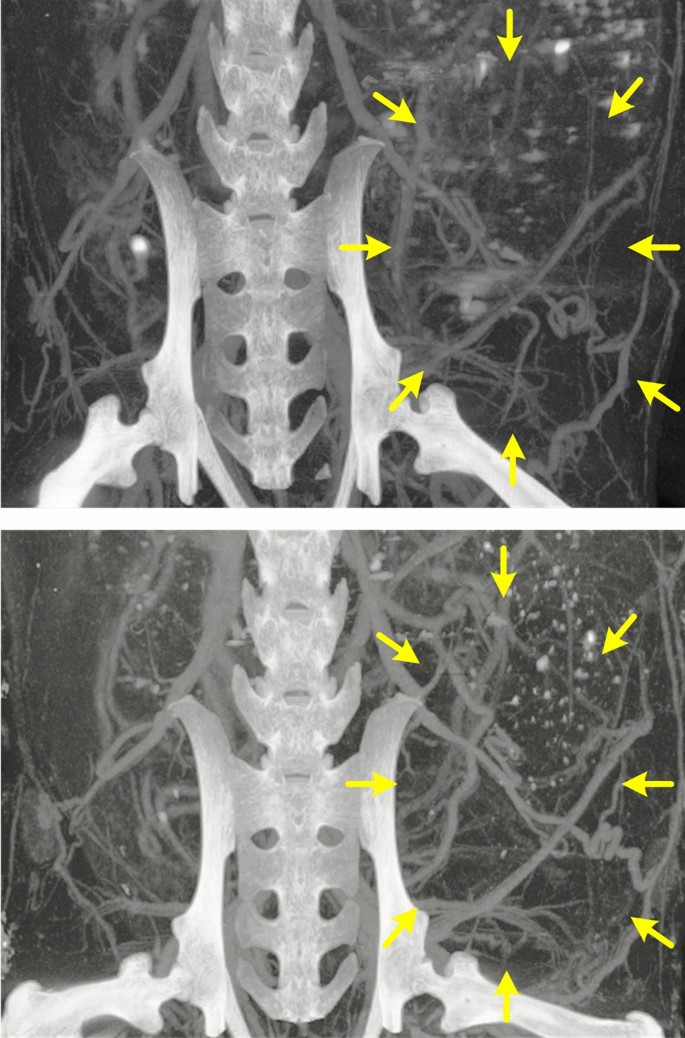

While simulations can provide insight into how microvascular networks may develop, the most conclusive validation method is the use of actual experimental data that captures tumor and microvasculature growth over a specific time period of observation. To determine accuracy of the predicted tumor size, data was collected from two mice at distinct time points. Preclinical in vivo microCT images of an aggressive breast cancer acquired in the same animal at reference baseline and 2 wks thereafter are presented in Fig. 5. These images highlight microvascular detail of the growing tumor, which were used as input features to the multiscale computational model. Here we used longitudinal data from this one subject for the prediction-based simulation and to discover the variable input to output mapping by reward maximization. The prediction-based simulation was then validated by using data from an untested second subject by making predictions on the constructed dataset. In short, simulated results were very similar to those derived from experimental images not used during the training process and otherwise previously unseen. More specifically, actual tumor measurements at 6 and 7 wks were 1.52 and 1.64 cm2, respectively. Similarly, relative growth and simulated tumor size over a matched 7-d period were found to be 1.49 and 1.78 cm2. Differences were attributed to the inherent stochasticity of the model processes (rather than a deterministic form).

Animals were anesthetized with 1 to 2% isoflurane in oxygen (V3000PK, Parkland Scientific, Coral Springs, FL) and placed on a temperature-controlled heating pad to maintain core levels (Rodent Surgical Monitor, AnimaLab, Poznan, Poland). A catheter was placed and secured in the tail vein before administration of a nanoparticulate contrast agent optimized for microCT angiography (200 µL; ExiTron nano 12000, Miltenyi Biotec, Bergisch Gladbach, Germany). This contrast agent has a long blood half-life enabling visualization of fine microvascular structures. After dosing, animals were transferred to a full body heated cradle and imaged using an ultra-high-resolution microCT system (OI/CT, MILabs, Utrecht, Netherlands). Exposure settings were 50 kV, 0.21 mA, 75 ms exposure time, and 360º rotation in 0.25º steps for a total of 1440 projections. Images were reconstructed using vendor software (PMOD Technologies LLC, Zurich, Switzerland) to a cubic voxel size of 20 μm, before saving as a DICOM format. DICOM files were then imported into OsiriX image analysis software (Pimeo, Bernex, Switzerland) for post-processing. The tumor microvascular network (contrast agent) was highlighted by rendering with a bandpass filter of 500 to 1000 Hounsfield Units (HU) (see Fig. 5). After global selection of the entire tumor space, a K-means clustering method was used to determine a topological structure of the microvascular network and to partition the microCT image into two mutually exclusive clusters (i.e., dark background and bright target blood vessel pixels)36. This automatic unsupervised vessel classification algorithm segmented the entire microCT image to isolate the microvascular network supporting tumor growth. These segmented images were then used as inputs to a multiscale mathematical model to forecast tumor growth.